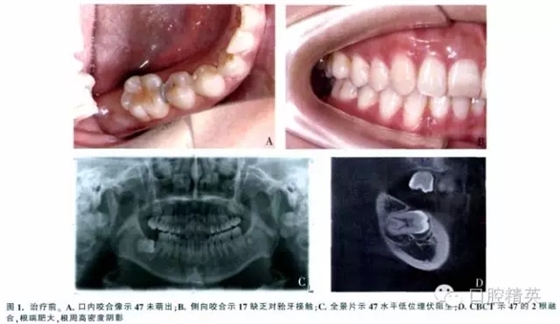

女,37歲,右下頜埋伏牙,要求治療。檢查示面型對(duì)稱,側(cè)貌正常。47未萌,17腭尖下垂,其余牙咬合好(圖1A、B)。全景片示:47水平低位埋伏,47冠方有一不完整的透明陰影,周圍呈現(xiàn)白色反應(yīng)線,根方有致密陰影(圖1C)。錐形束CT(CBCT)示47接近水平位,牙長(zhǎng)軸與牙合平面前上方夾角約為75°,根尖端肥大,牙周膜間隙模糊(圖1D)。